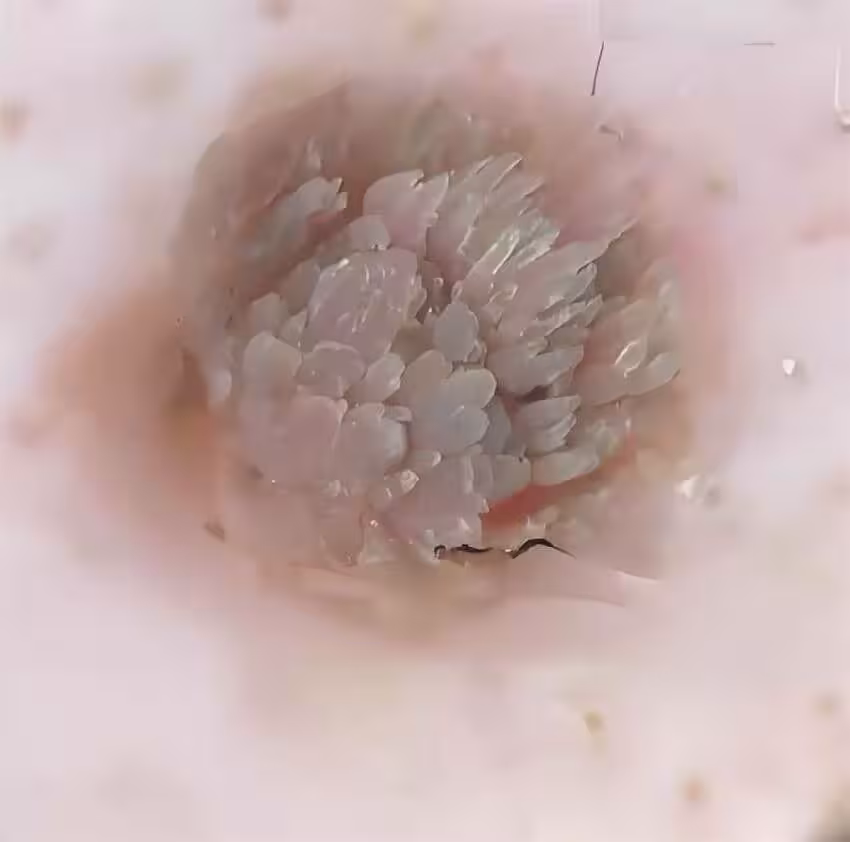

女子旅遊回來手上突現「菜花」硬塊!剪開瞬間嚇懵,醫生急喊: 酒店這些「隱形雷區」打死別碰!

所有人都倒吸一口涼氣——內部竟是密密麻麻的黑色絲狀物,像極了腐爛的菜花莖稈。

「這是典型的傳染性軟疣合併真菌感染!」主治醫師王主任面色驟變,「您最近是不是住過酒店?」